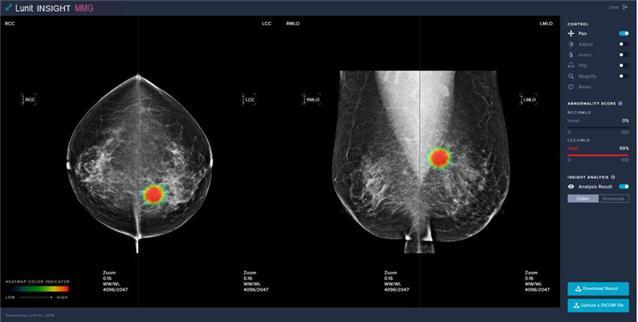

[세종=뉴시스] 유방암 의심 부위를 자동으로 검출하는 인공지능 기반의 '유방암영상검출·진단보조소프트웨어'. (사진=식약처 제공) *재판매 및 DB 금지